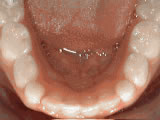

Missing Teeth Replacement

Patient was missing lateral incisors; braces for 20 months aligned the teeth, followed by bonded “Maryland” bridges to replace the missing ones.

Missing lateral incisors before